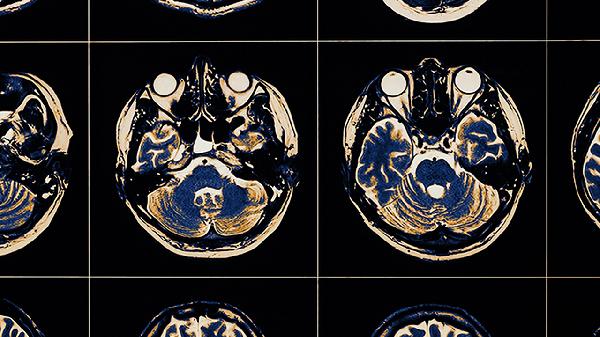

脑血栓患者去世前可能出现意识障碍、呼吸异常、瞳孔变化、血压骤降、四肢冰冷等征兆。这些表现通常与脑干功能衰竭或多器官功能衰竭有关,需立即采取医疗干预。

意识障碍是脑血栓终末期的常见表现,患者可能从嗜睡逐渐发展为昏迷,对外界刺激无反应。部分患者会出现谵妄或烦躁不安,可能与脑缺氧或颅内压增高有关。呼吸异常表现为呼吸频率不规则,如潮式呼吸或长吸气呼吸,提示延髓呼吸中枢受损。瞳孔变化包括双侧瞳孔散大固定或不等大,反映脑干受压或疝形成。血压骤降通常伴随心率减慢,显示心血管调节中枢功能丧失。四肢冰冷伴皮肤花斑样改变,是外周循环衰竭的典型表现。